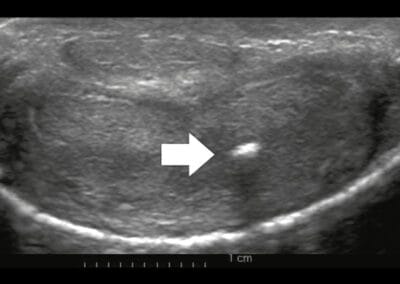

Sexuelle und psychologische Beratung ist ratsam, bevor eine endgültige Entscheidung getroffen wird. Eine realistische Vorstellung des Patienten ist wichtig, um eine Entscheidung zu treffen. Die klinische und Ultraschalluntersuchung sowie ein SKAT Test, um die Kurve und deren Winkel zu dokumentieren, sind Voraussetzung für die Auswahl der Behandlungsmodalität. Die Penisaufrichtung wird stationär durchgeführt.

© Dr. Aref Elseweifi / masculine.de